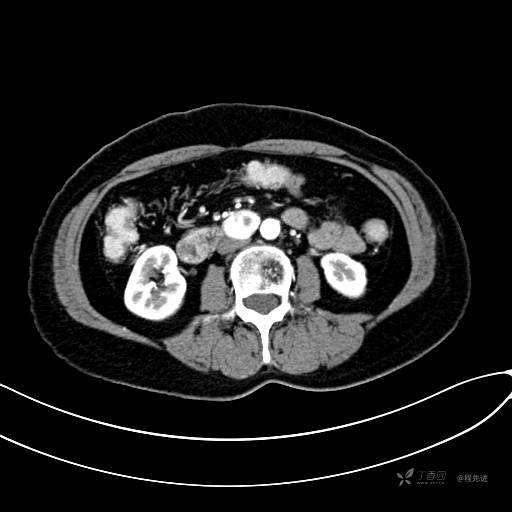

CT平扫